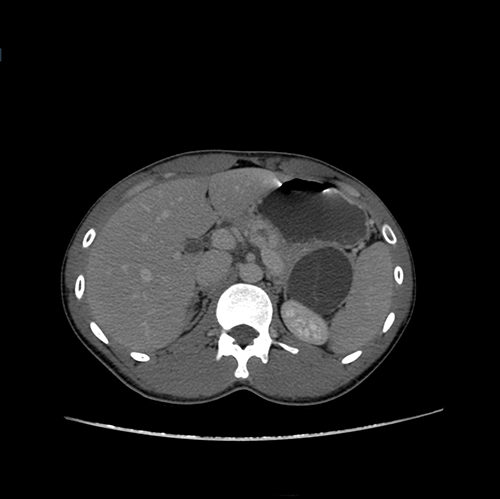

胰尾囊腺瘤---腹腔镜胰尾切除